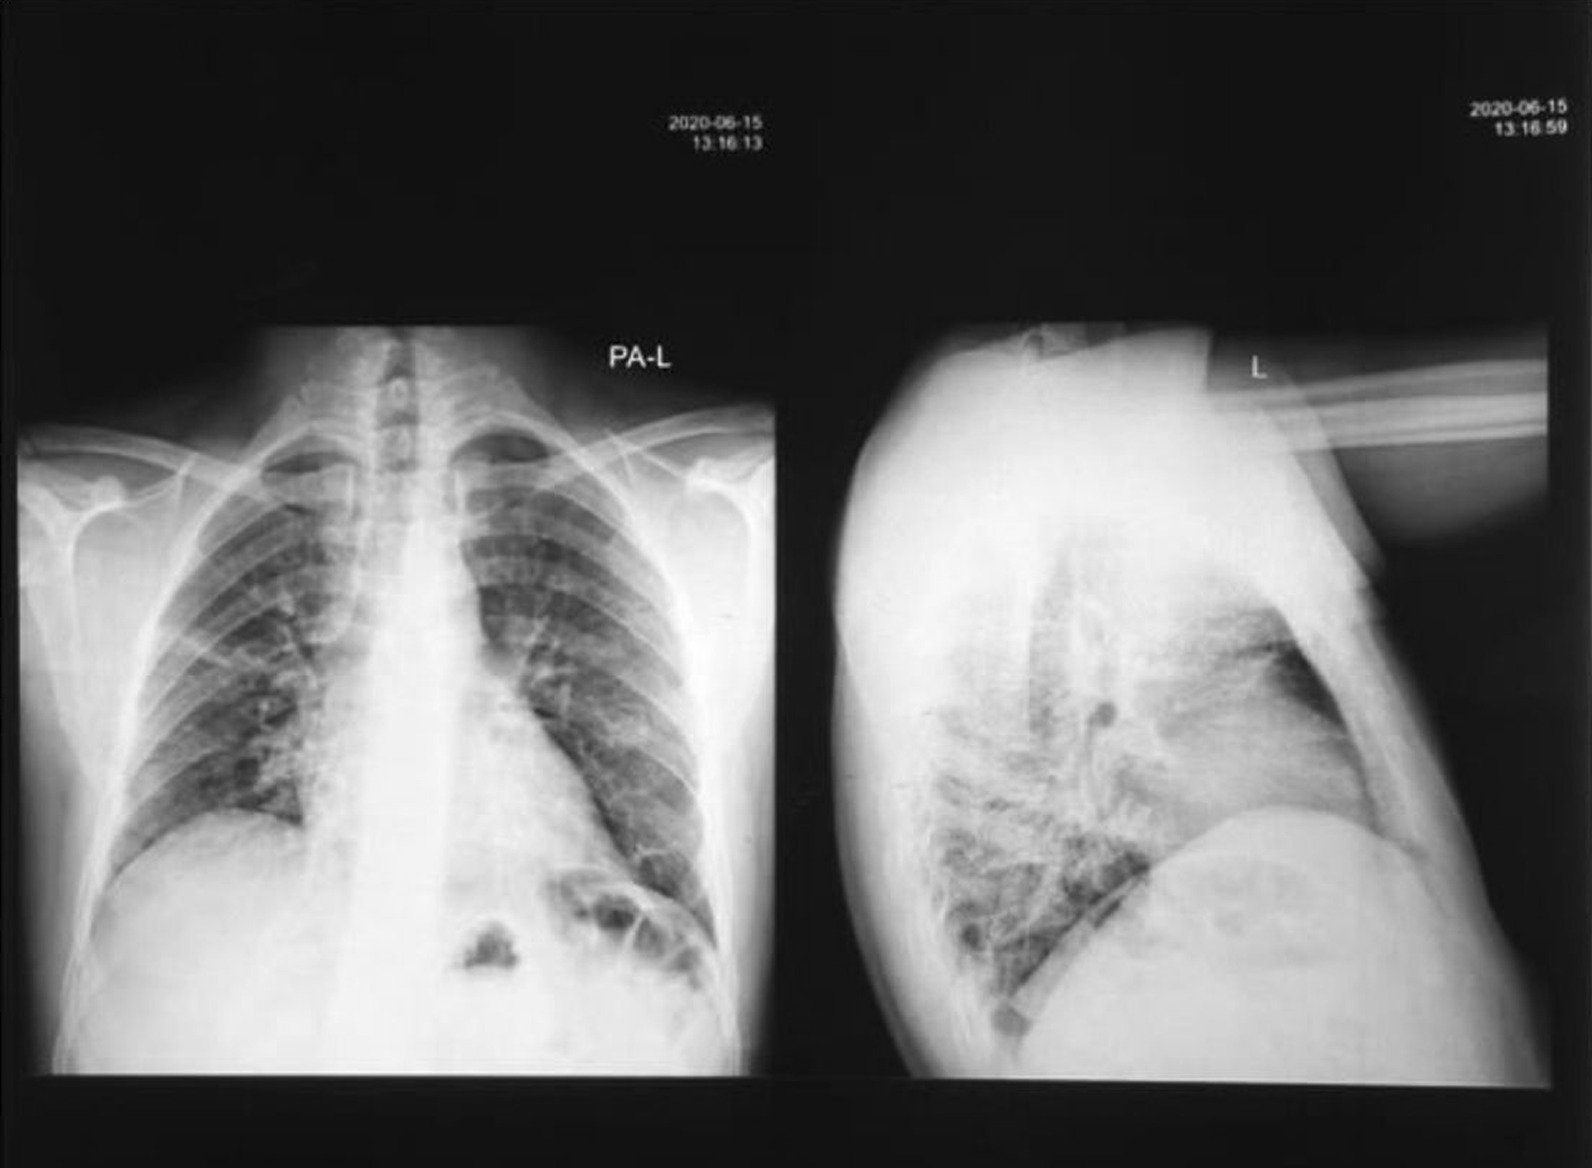

Fig. 1.

Anteroposterior/longitudinal chest X-ray (CXR AP/L). Imaging performed 10 days after COVID-19 presentation shows patchy infiltrates with ground-glass opacifications